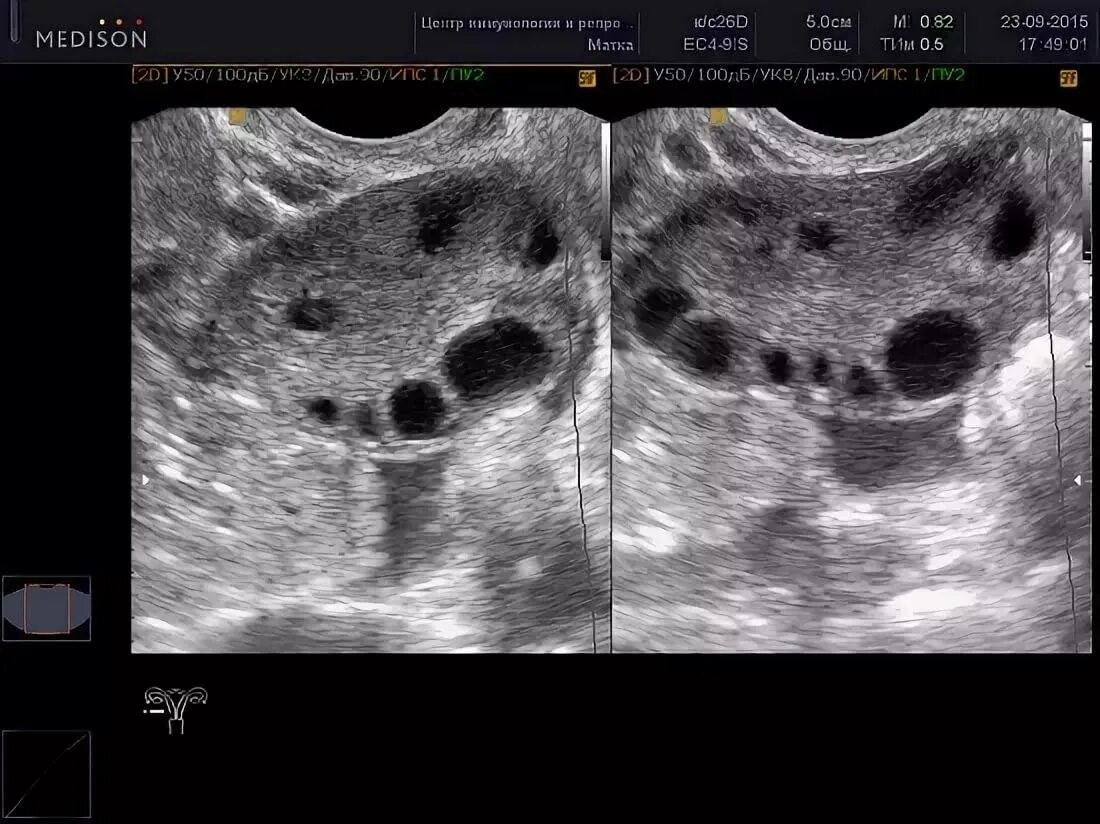

Яичник 8 см